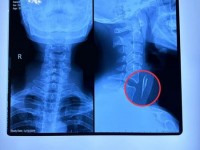

Như trước đó chúng tôi đã thông tin về trường hợp bệnh nhân X bị hóc xương đến khám, kết quả cận lâm sàng cho thấy có dị vật mắc ở thực quản (ảnh phim chụp) từ chối điều trị mặc dù đã được giải thích cặn kẽ về các biến chứng.